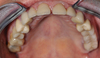

Restauration complète maxillaire et mandibulaire

Couronnes céramiques sur incisives latérales et facettes sur incisives centrales